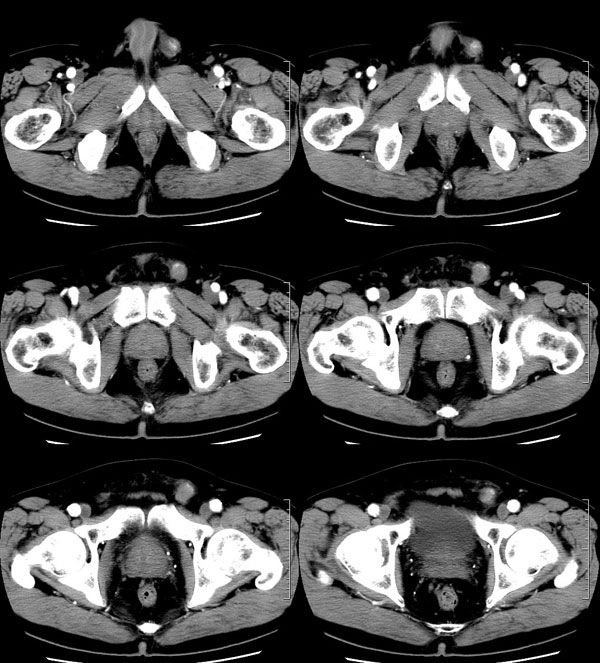

| 男性,69岁。自2个月前开始无意中发现左侧阴囊内一鸡蛋大小肿物,当时无伴疼痛等不适,未予重视。肿物逐渐增大,近段时间常伴左会阴部、腹股沟区牵扯不适,并于2周前在我院门诊行彩超检查提示“左侧附睾肿瘤可能,左侧睾丸鞘膜积液”。 专科检查:左侧阴囊肿大,其内可触及一鹅蛋大小肿物,表面光滑。肿物前部呈囊性感,后部质硬,按压无疼痛,无缩小,活动度良好。左侧睾丸未触及,透光试验(±)。                 王仕学发言:左侧睾丸见一密度不均肿块,边缘清楚,周围见水样密度影;考虑睾丸生殖细胞性肿瘤可能性大. 睾丸肿瘤占生殖系统肿瘤的3%-5%,占男性恶性肿瘤的0.5%-1.0%,其中生殖细胞性肿瘤占95%.睾丸肿瘤包括生殖细胞和非生殖细胞肿瘤两大类,前者占95%以上,后者不到5%.非生殖细胞肿瘤虽少见,但种类繁杂,主要有支持细胞、间质细胞和支持细胞-间质细胞瘤等功能性肿瘤,和间皮瘤、腺癌、横纹肌肉瘤、粘液性囊腺瘤、纤维上皮瘤、黑素神经外胚瘤、淋巴瘤等附属组织肿瘤。不同的病理类型的睾丸肿瘤发病率高峰不同,睾丸癌多发于35岁以前,精原细胞瘤发病高峰为30-35岁。精原细胞瘤约占睾丸肿瘤的60%,发病高峰在30-35岁。85%的患者睾丸有明显肿大,肿瘤局部侵犯力较低,肿瘤一般有明显界限。 手术:行“左侧附睾、睾丸、精索切除术”。 病理诊断:(左睾丸、附睾)肿物,为低分化腺癌。另送检(左精索远端)肿物,镜下亦为低分化腺癌。 免疫组化:ck(l)(++++)、cea(+++)、ca19-9(-)、psa(-)、plap(-)、p53(-)、vimentin(-)。 原贴地址:http://www.radinet.com.cn/forum_view.asp?forum_id=4&view_id=30707 |